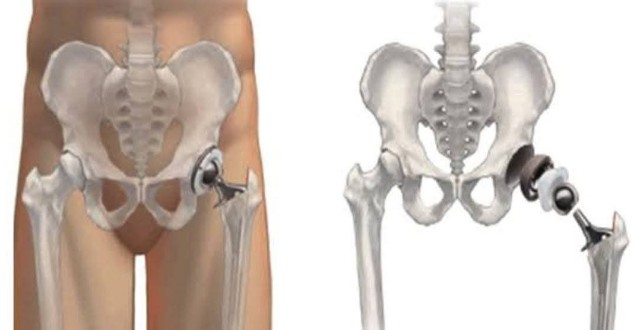

人工股関節

退院して一番困ること 人工股関節の寿命は約30年 経年劣化によるものか 平均的使用頻度によるものかわかりません 多分両方 ということは できるだけ負荷をかけない 即ち動かさないほうが良い がシモ 入院中はでたことを告げると 看護師が適切に処理してくれます が退院すると 自分でLavatoryに立たなくてはなりません すると股関節を動かします この二律背反が葛藤の種 立たないと 気色悪いことに 立つと人工股関節に負担が まぁそれも慣れました